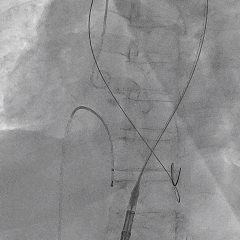

患者病史 主诉:发作性胸闷憋喘半年,加重伴呼吸困难2周。 现病史:患者半年前无明显诱因出现胸闷、憋喘,伴有下肢水肿,2周前上述症状明显加重,夜间不能平卧,痰中带血丝,为进一步诊治再次来我院,门诊以"心力衰竭"收入院。 既往史:肾功能不全、心房颤动 心脏超声提示:LVEF:0.54 1.主动脉瓣病变;2.主动脉瓣狭窄(重度)并反流(中度);3左室壁节段性运动不良;4.升主动脉扩张、双房扩大、左室肥厚;5.二尖瓣硬化并反流(中度);6.三尖瓣反流(轻-中度);7.肺动脉瓣反流;8.肺动脉高压(轻度)PGmean=105mmHg,Vmax=635cm/s,瓣口面积0.27cm²。 术前CT评估 Type0型二叶瓣,重度钙化,钙化集中在瓣叶游离缘,右冠窦为著;左冠高度11.8mm,由于左冠窦部空间较小,左冠风险较高, 升主动脉扩张,最宽处50.5mm;主动脉瓣环水平夹角61.5°,横位心。主动脉弓角77.6°,锐角弓,外周入路在腹主及髂总处有大量散状钙化,胸主处有81.6°的迂曲。 手术策略 推荐右侧股动脉为主入路,左侧股动脉为辅入路,送snare辅助过弯,使用18F大鞘,推荐预装ProStyle A® AV23瓣膜,20mm球囊预扩,初始定位对齐真实瓣环瓣上5mm超高位初始定位释放,释放过程中使瓣膜自然下滑,到工作位观察瓣膜形态,最终理想位置0-瓣下3mm。 手术过程 Step1:右侧股动脉为主入路、左侧股动脉为辅入路,成功穿刺并送入 18F 大鞘; Step2:主动脉根部造影,瓣口限制重 Step3:Type 0 型二叶瓣畸形合并重度钙化,患者瓣口狭窄严重,同时横位心,不仅导丝跨瓣困难,导管更难进入;术者凭借精湛操作,将导丝顺利跨瓣,反复微调导管角度,最终导管顺利过瓣。 导丝精准跨瓣 Step4:20mm球囊跨瓣困难,snare辅助下球囊成功跨瓣,预扩有腰无漏,冠脉充盈良好。 Step5: snare辅助下成功跨瓣,可以看到系统过弓形态瓣膜仓柔软,过弓顺滑 输送系统过弓 Step6:初始定位瓣上5mm开始释放,释放部分后观察瓣架下缘内收明显,后回收系统重新定位 初始定位 底部内收 Step7:瓣膜完全释放前,血压一度降低,术者迅速调整器械,实现瓣膜迅速锚定,快速释放 完全释放 Step8:20mm球囊后扩 最终造影,位置(瓣下3mm)形态良好 手术难点 患者不仅有主动脉瓣重度狭窄,还叠加肾功能不全、心房颤动等基础疾病,术中血流动力学波动极易引发心功能衰竭。ProStyle A® 预装干瓣“开包即用” 的特性压缩了术者操作时间,80%可回收设计给了术者容错空间,而这些看似难以逾越的难关,最终被团队精湛的医术一一化解,术中对于导丝、导管、球囊等器械每一步的精准操控,再到突发状况的从容处置,无不彰显着团队深厚的专业积淀与顶尖的操作技艺。 结语 此次手术的圆满成功,不仅彰显了陈玉国、李传保教授团队在复杂结构性心脏病介入治疗领域深厚的专业造诣与攻坚克难的决心,也充分验证了ProStyle A®系统在应对复杂高难度病例时的卓越适用性与有效性。 作为扎根齐鲁、享誉全国的医疗高地,山东大学齐鲁医院始终赓续着这片热土的仁厚文脉,将“医道从德,术业求精”的院训精神镌刻在每一次诊疗实践之中。特别是在结构性心脏病诊疗领域,医院团队始终怀揣医者担当,勇攀医学高峰,不断以更前沿的技术突破,为危重患者点亮重获新生的希望。 专家简介 陈玉国 山东大学齐鲁医院(点击查看专家详细简历) 李传保 山东大学齐鲁医院(点击查看专家详细简历) · END ·